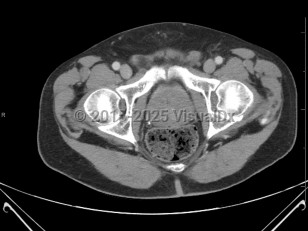

Benign prostatic hyperplasia

Synopsis

Management includes modifications in routine (limiting fluids at bedtime, caffeine intake, and diuretics) and medications. BPH can cause acute urinary retention, which requires catheterization. Patients with poor results may seek surgical treatment such as prostatic urethral lift, transurethral resection of the prostate, transurethral incision of the prostate, or prostate laser surgery.